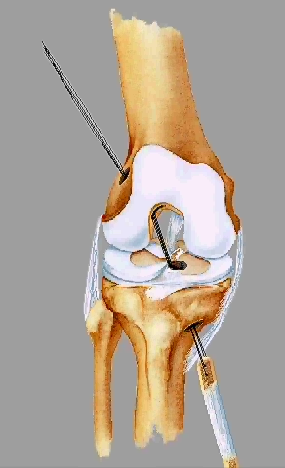

ACL定位器

准确放置ACL定位器

股骨导针为直径1mm克氏针

股骨定位器与股骨导针

准确放置股骨定位器

按照左膝1点、右膝11点 (髁间窝后顶为12点)定位的基本方法定位,在能够保证骨道后壁完整的前提条件下,尽可能向后接近过顶处。

股骨引导器引导下,钻股骨导针

制作股骨隧道

股骨骨道深度一般为:2.2~2.7cm

清理骨道内残渣,检查骨道四壁的完整性